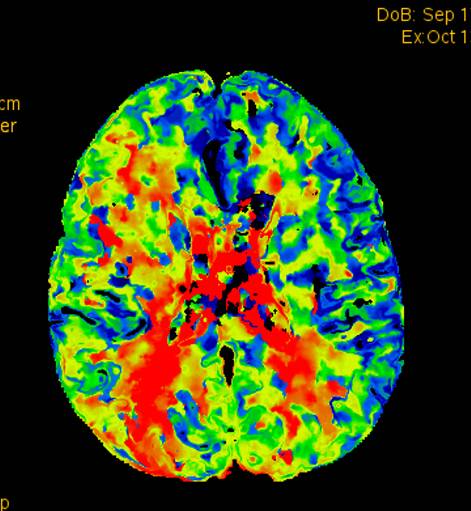

术后2个月患者未再诉右眼黑曚。复查CTP示:颅内灌注明显改善。

术前灌注成像,右侧大脑半球灌注较差。

此次分享两例颈动脉闭塞复合手术开通病例。第一例为颈内动脉长段闭塞,从颈内动脉起始段开始闭塞。患者术前存在眼动脉缺血事件及右侧半球灌注不足。颈内动脉剥脱后,颈内动脉可淡淡显影,为微导管通过创造条件。微导管通过后,顺利完成球囊扩张及支架植入,完全开通右侧颈内动脉。第二例为右侧颈总动脉闭塞患者,虽有颈外动脉代偿,但仍存在TIA及右侧大脑半球灌注不足。经颈动脉内膜剥脱后,造影可见颈总动脉显影,但管腔严重不规则,经球囊扩张及支架植入后,颈总动脉显影好。两例患者术后7天复查颈动脉CTA,均显示颈内动脉起始处较术后造影增粗。